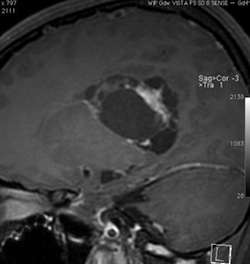

無症状の若い女性に偶然発見された例

central neurocytomaは腫瘍実質部分が多いものです。しかし,この例のように腫瘍の大部分をのう胞が占める症例もあります。

anterior transcallosal apprroachで亜全摘出しました。20代の女性でしたが,その後,子どもも生まれて元気です。

腫瘍の位置から,透明中核が発生母地であることが推測されます。central neurocytomaは,惻脳室壁にべとべとくっつくので,脳質上衣からの剥離は簡単ではありません。鑑別しなければならないのが,成人の毛様細胞性星細胞腫ですが,この症例では決定的な鑑別点はないでしょう。のう胞性の毛様細胞性星細胞腫と同様に,腫瘍の増殖力は低く無理して全摘出するものではありません。